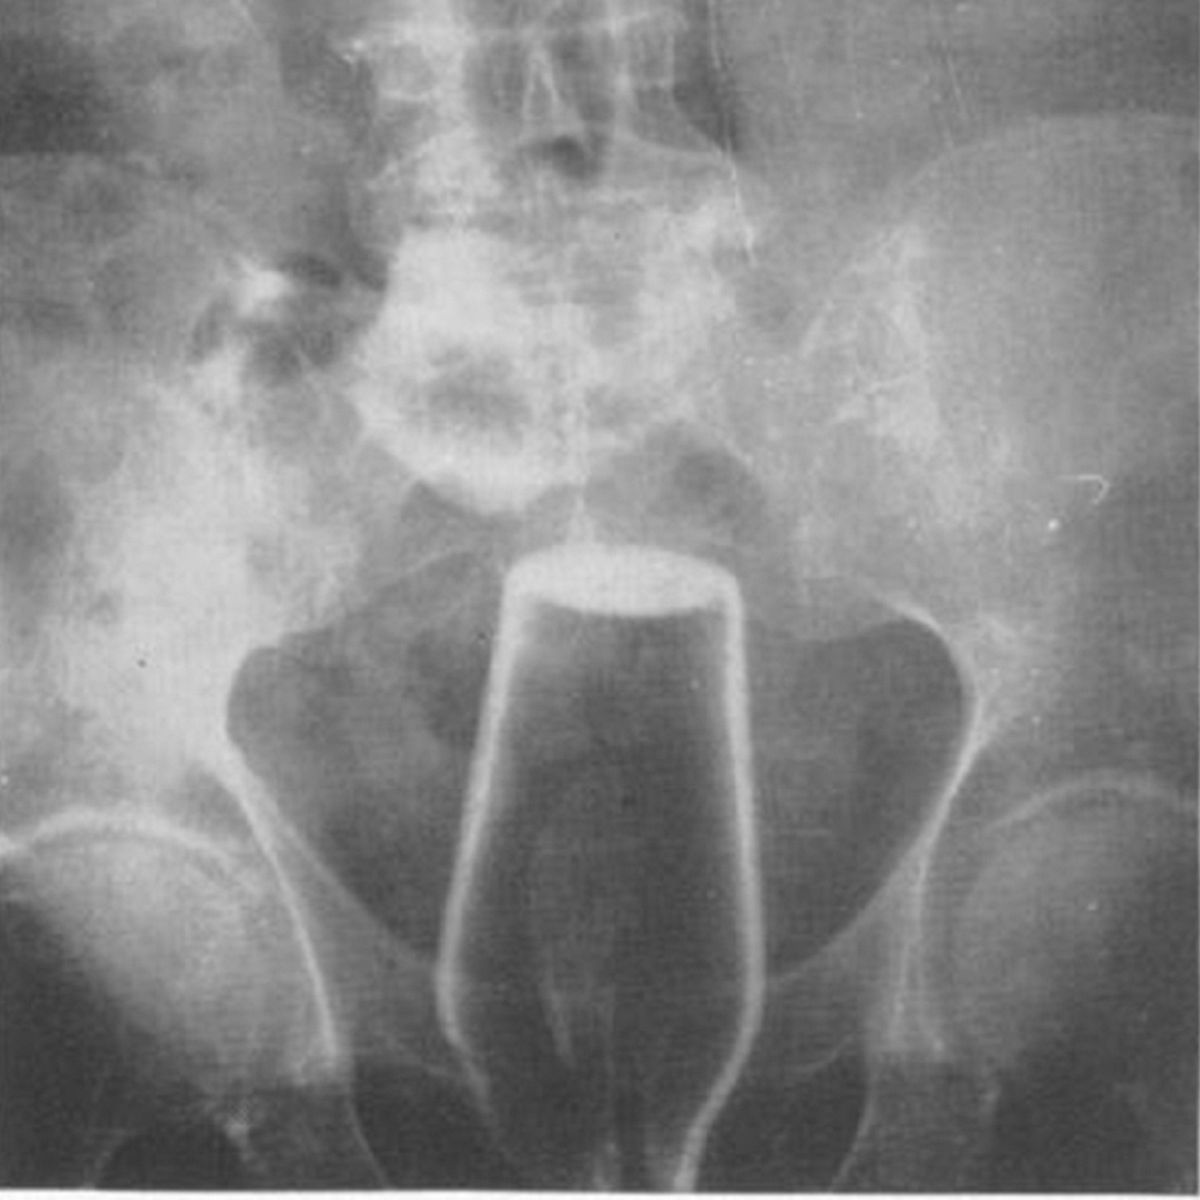

Lekarze, do których przyszli ci pacjenci na pewno nie mogli uwierzyć w to, co zobaczyli na zdjęciach. Jeszcze dziwniejsze były tłumaczenia. Ten pacjent, u którego znaleziono butelkę tłumaczył, że potknął się w okolicach śmietnika i naczynie samo dostało się do jego odbytu.